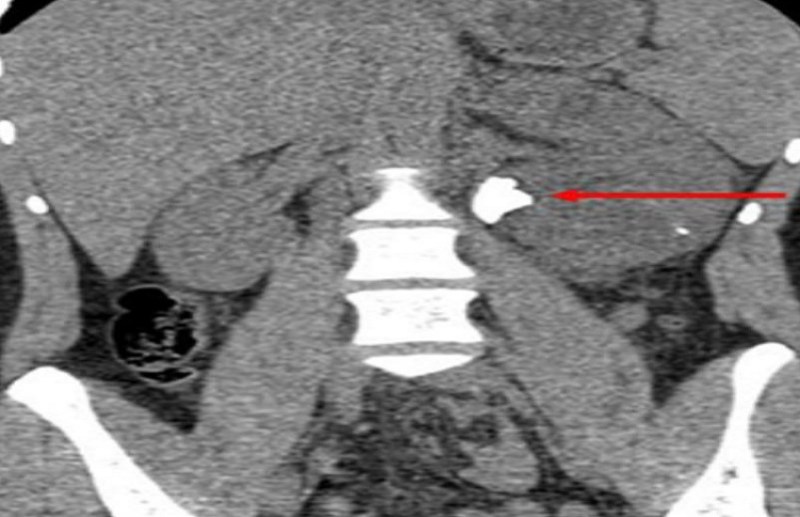

बनारस हिंदू विश्वविद्यालय के चिकित्सा विज्ञान संस्थान के यूरोलॉजी विभाग के असिस्टेंट प्रो डॉक्टर यशस्वी सिंह ने बताया कि पूर्वांचल में पहली बार एक 21 महीने के बच्चे के बायें गुर्दे की पथरी का सफलतापूर्वक दुर्बीन विधि से ऑपरेशन किया गया। इस प्रक्रिया को "ट्यूबलेस मिनी परक्यूटेनिया नेफ्रोलिथोटॉमी" कहा जाता है और इस प्रक्रिया को छोटे बच्चों में करना अत्यंत ही जटिल एवं प्रतिनिधि ऑपरेशन है। उन्होंने बताया कि इस ऑपरेशन से 3×2 सेमी की पथरी निकाली गई।